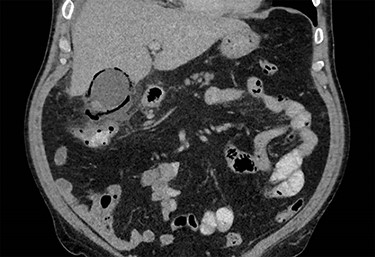

On presentation to the emergency department, the patient was tachycardic and febrile and his serology showed a neutrophilia, elevated CRP and bilirubin with normal hepatic transaminases. On examination, he was focally tender with voluntary guarding in the right upper quadrant. A CT abdomen was performed which identified a distended gallbladder, with adjacent gas locules and fat stranding around the hepatic flexure. The differentials included a contained microperforation at the hepatic flexure or emphysematous cholecystitis. The patient was haemodynamically stable and therefore a period of non-operative treatment was pursued. The patient was commenced on IV ampicillin, metronidazole and gentamicin, strict fluid balance, nil by mouth with regular clinical reviews. On Day 3, the patient had shown minimal clinical improvement and a progress CT was obtained which revealed extensive gas within the gallbladder wall and adjacent-free fluid consistent with emphysematous cholecystitis (Figs 1 and 2).